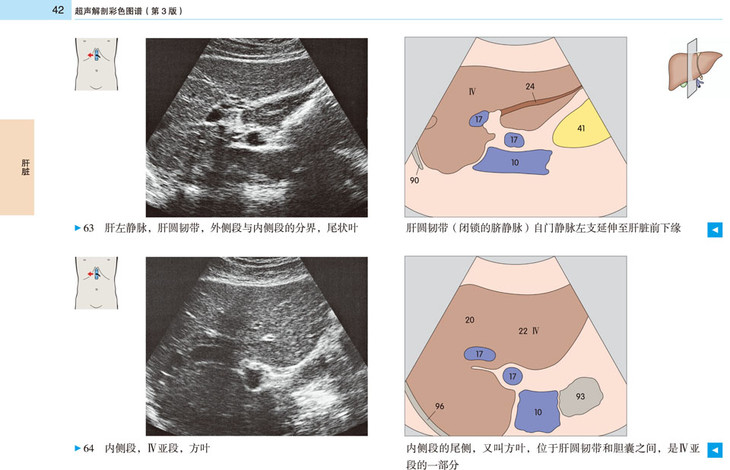

本书提供了全新的、高质量的超声图像和示意图,标示清晰、色彩丰富,为初学者带来极大的帮助。展示了腹部、盆部、甲状腺超声的所有标准切面和扫描路径,标示了各解剖结构和间隙在三维空间的解剖细节及其与超声的关系;并展示了探头定位,以及生成的截面图像、解剖结构、扫描平面在器官中的位置。本书作为优秀的初学者向导,适用于医学生、超声科医师、临床各科医师。